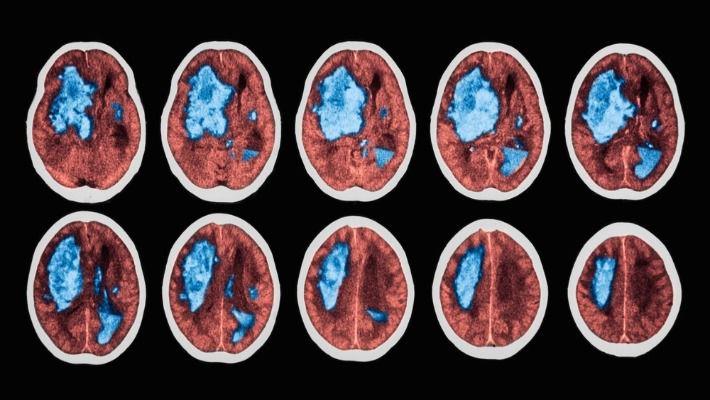

מיליוני אנשים ברחבי העולם לוקים בשבץ מוחי. שליש מהם מתים ומחצית מהנותרים נשארים עם נכות קבועה. במדינת ישראל, שבץ מוחי היא סיבת המוות החמישית, כשבכל שנה כ- 18,000 איש סובלים ממנה. כאשר מגיע מטופל עם שבץ מוחי לבית החולים ולאחר שקיבל את הטיפול התואם מתבצע בירור לסיבת השבץ. בחלק מהחולים קיימות מחלות רקע דוגמת יתר לחץ דם, יתר שומנים בדם, סוכרת ומחלת לב איסכמית, אך בלפחות 25% מהמטופלים לא נמצאת סיבה ברורה לאירוע מוחי, וזאת גם לאחר בירור.